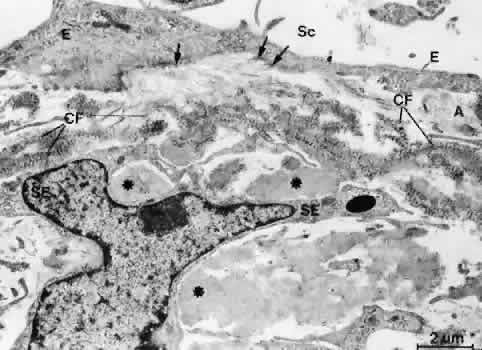

Serial tangential sections showed in the electron microscopic dimension that the fiber network belongs to a complicated system that connects the inner wall endothelium with the trabecular lamellae. The elastic-like fibers of the cribriform layer form a regularly arranged network of interlacing fibers that are continuous with the elastic-like fibers of the adjacent corneoscleral lamellae (Fig. 13). Toward the inner wall endothelium, bundles of fine fibrils separate from the elastic-like fiber sheaths and connect the subendothelial network of elastic-like fibers either with the endothelium of Schlemm's canal or with the subendothelial basement membrane material. Therefore, these fibrils were called “connecting fibrils” (Fig. 14).22 In the adult eye, the connecting fibrils are embedded in a homogeneous ground substance that is digestible with chondroitinases.14

Fig. 14. Electron micrograph of an oblique sagittal section through the inner wall of Schlemm's canal. The connecting fibrils (CF) derive from the sheaths of elastic-like fibers and are attached to the cell membranes of the inner wall endothelium (E, arrows). Asterisks indicate plaque material. A, subendothelial fine fibrillar material; Sc, Schlemm's canal;SE, subendothelial cells. (Rohen JW, Futa R, Lütjen-Drecoll E: The fine structure of the cribriform meshwork in normal and glaucomatous eyes as seen in tangential sections. Invest Ophthalmol Vis Sci 21:574, 1981)